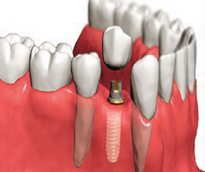

İmplant (Diş kökü olmayan bölgelere uygulanan suni kökler)